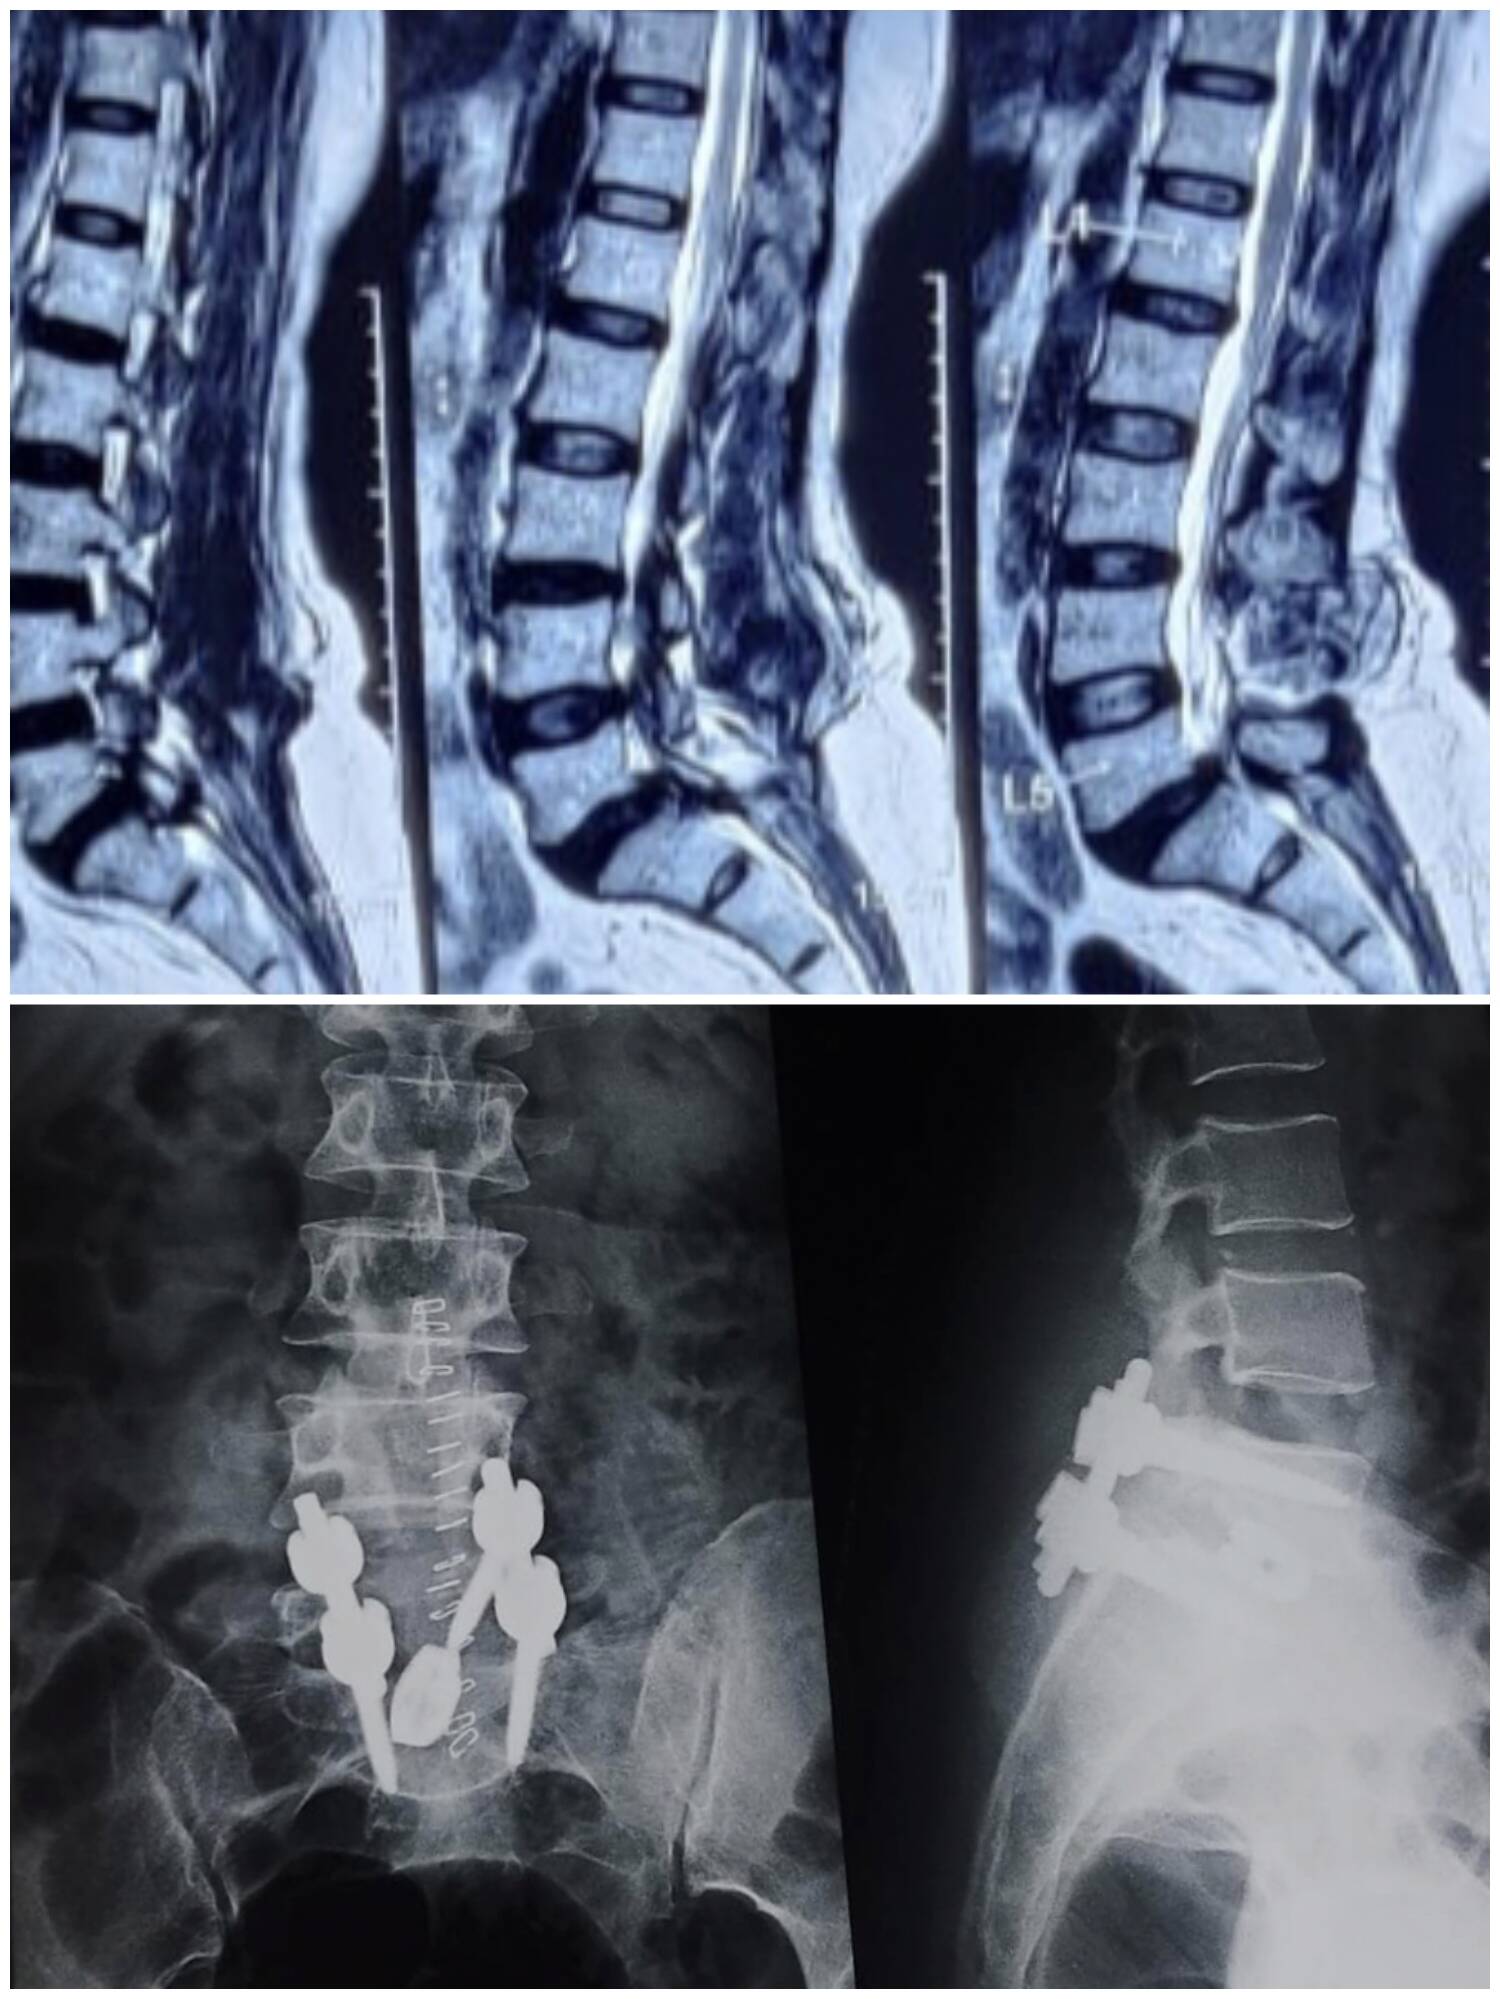

The damaged or slipped disc is removed.

A cage (spacer) filled with bone graft is placed between the vertebrae.

Screws and rods are fixed to support the spine.

Over time, the bone graft fuses the two bones, giving permanent stability.